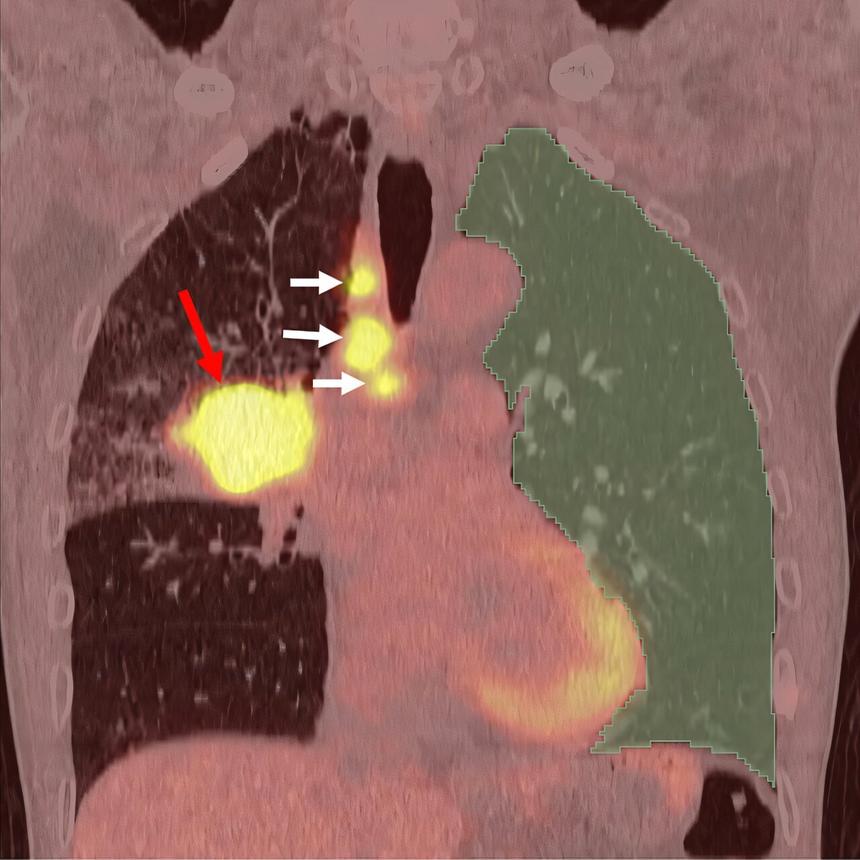

Группа ученых из Университета Ниигаты представила новое исследование, в котором искусственный интеллект (ИИ) используется для анализа изображений PET/CT, чтобы предсказать развитие интерстициальной болезни легких — серьезного побочного эффекта иммунотерапии при раке легких. Это открытие было опубликовано в журнале Academic Radiology.

Исследование охватило 165 пациентов с первичным раком легких, которые проходили иммунотерапию в Медицинской и стоматологической больнице Университета Ниигаты. Ученые предположили, что пациенты с сильным воспалением в здоровых легких до начала лечения иммунотерапией имеют более высокий риск развития интерстициальной болезни.

Используя PET/CT-сканирование, ученые смогли оценить степень воспаления в здоровых участках легких и применили ИИ для анализа этих данных. Результаты показали, что риск развития болезни в 6,5 раз выше у пациентов с высоким уровнем воспаления в тканях легких по сравнению с теми, у кого воспаление было минимальным.